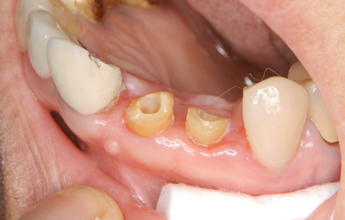

右の前歯二本がボッキリおれてしまいました。幸い歯の根っ子は折れていませんでしたから、抜歯せずに残せそうですが.........

歯が折れて根っ子が少しだけ歯茎からでている状態。

虫歯でもそうですが、こうなるとこのまま差し歯をいれてもすぐ外れるといったトラブルが起こります